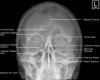

- Adult Facial Bones - Occipitomental(Waters) View

(1) Dolan & Jacoby’s line

| 1 : Orbital line 2 : Zygomatic line 3 : Maxillary line |